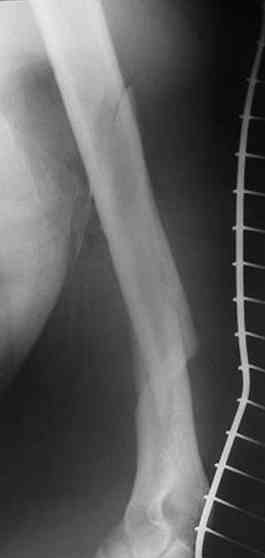

В нашем случае 21 летний боец уличного фронта, фиксацию провели на следующий день, зафиксирован интрамедуллярным штифтом. Не стали делать первичную хирургическую обработку точечной раны, зафиксирован как есть. Клинические снимки:

Конечно, наш случай не эталон, возможно, на месте вам виднее, может быть, нет необходимости ориентироваться на зарубежные ссылки, если получается лечить аппаратом Илизарова на месте, почему нет? Необходимо посмотреть собственный арсенал, чем фиксировать, и какая теория, иначе любой отличный метод можно превратить в источник остеомиелита.